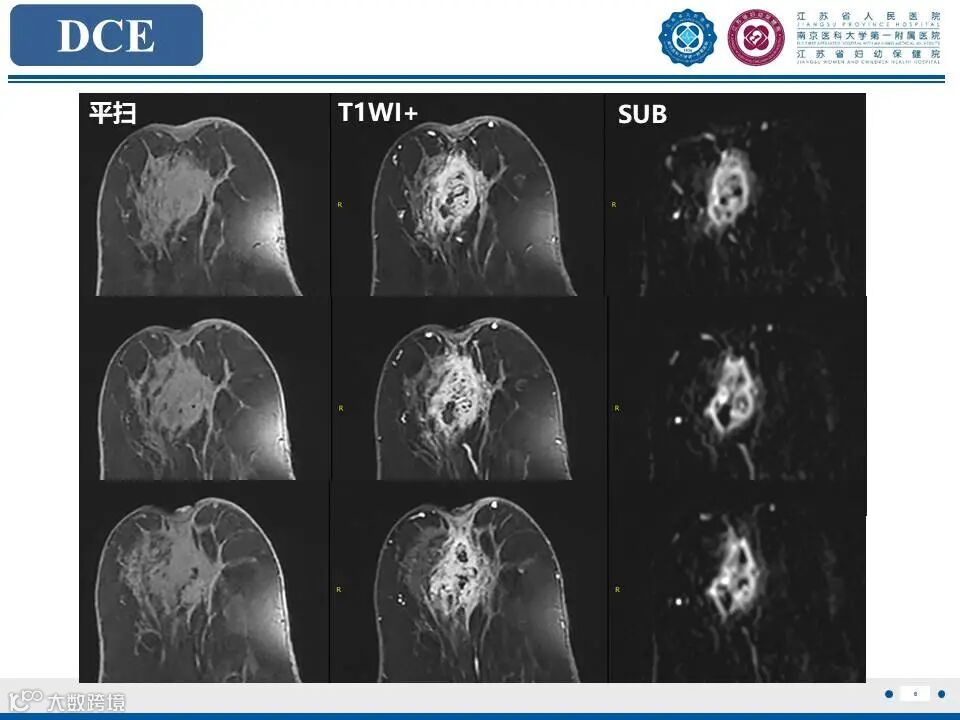

非哺乳期乳腺炎